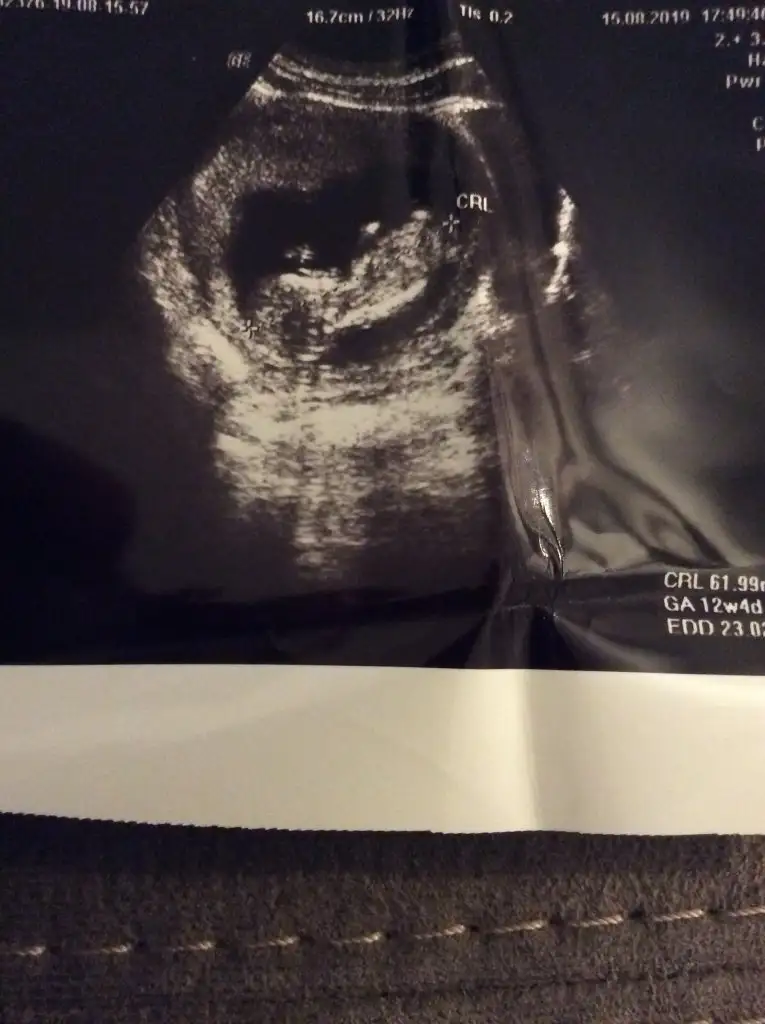

12+2 deyizİlk usg de kafa şekline erkek diyorum kaç haftalık burda 11 yada 12 hafta olmalı nub için

Çift yumurta ikizi mi bunlar? Görüntüler hiç net değil maalesef.ama ben sağdaki usg yi erkeğe.soldakini de kıza benzettim kafa yapılarını.yada ikiside erkek olabilir ,evet evet ikiside erkek diyorumbunlarda benim bebişlerimin 12haftalık görüntüleri.Daha önce 10haftalık koymuştum.çok net değildi

Biri kız biri erkeksordum ama daha erken dedibi de şimdi bunları ,çektim videodan belki yardımcı olur

Canım soldaki kız sağdaki erkek.foto da soldakinden emin olamamıştım videoda daha net.nub çizgisi göremiyorum.kafa yapılarına göre yorum yaptım.sonucu öğrenince yazarsınsordum ama daha erken dedibi de şimdi bunları ,çektim videodan belki yardımcı olur

teşekkürler canım.öğrenince yazacağımCanım soldaki kız sağdaki erkek.foto da soldakinden emin olamamıştım videoda daha net.nub çizgisi göremiyorum.kafa yapılarına göre yorum yaptım.sonucu öğrenince yazarsın